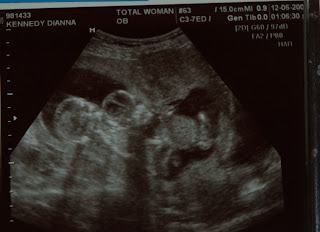

For it was you who formed my inward parts; you knit me together in my mother’s womb.

I praise you, for I am fearfully and wonderfully made. Wonderful are your works; that I know very well.

My frame was not hidden from you, when I was made in secret, intricately woven in the depths of the earth.

Your eyes beheld my unformed substance.

In your book were written all the days that were formed for me, when none of them as yet existed,

For me, this is such a powerful passage. It calls to mind that before we are born, or even conceived, God knows us, and has plans for our lives. As a mother, it warms my heart that my children are protected by God, even before I am aware of their existence. As a woman, it’s a reminder that I am a vessel for God’s desires — both for myself, and my children.